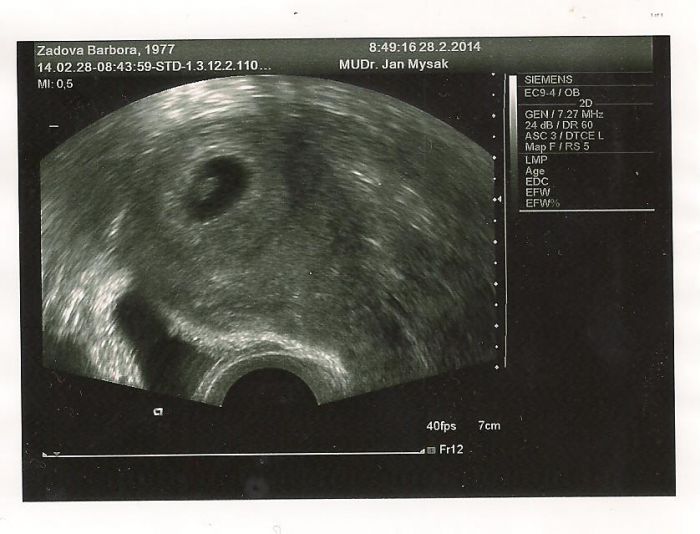

Když jsem na tom PC tak vám sem dám foto utz z 28.2. to jsem podle něj byla 6plus6.

[481917]

Baruš, fotka krásná. Už se nemůžu dočkat zítřka na tu svoji. Snad bude vše OK...